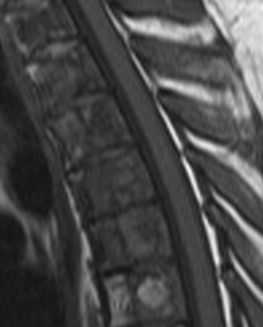

МРТ позвоночника. Т2-взвешенная сагиттальная МРТ. Желатинозная трансформация при нарушении питания.